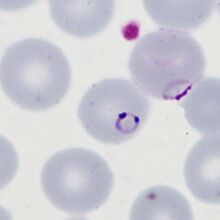

The early trophozoite

For P.falciparum this stage is characterised by fine ring forms with few other changes to red cell or parasite.

- Ring forms are fine and delicate and may be the sole form present (synchronicity)

- Frequently the red cells contain multiple parasites

- Parasites may have a distinctive "double dot" or signet ring form

- Parasites may appear on the accolé forms that appear flattened against the cell membrane

- Affected red cells have normal size and haemoglobin content

P.falciparum early trophozoites